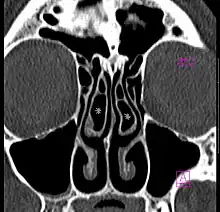

Concha bullosa bilatérale en scanner (coupe coronale)

Il s'agit d'une variante anatomique fréquente, retrouvée chez près de la moitié de la population[2]. Elle est bilatérale dans la moitié des cas[2].